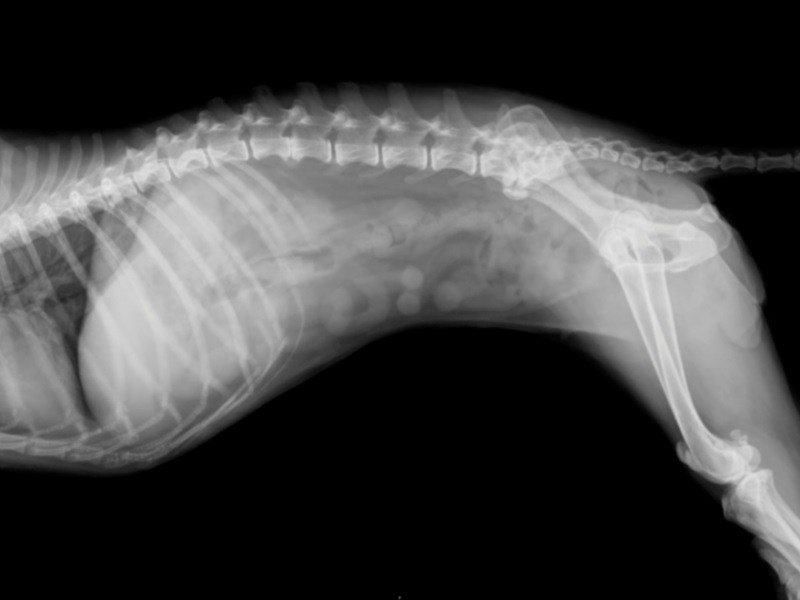

• spinal disorders;

• congenital pathology of the hip joint - dysplasia.

Dysplasia

Spinal diseases